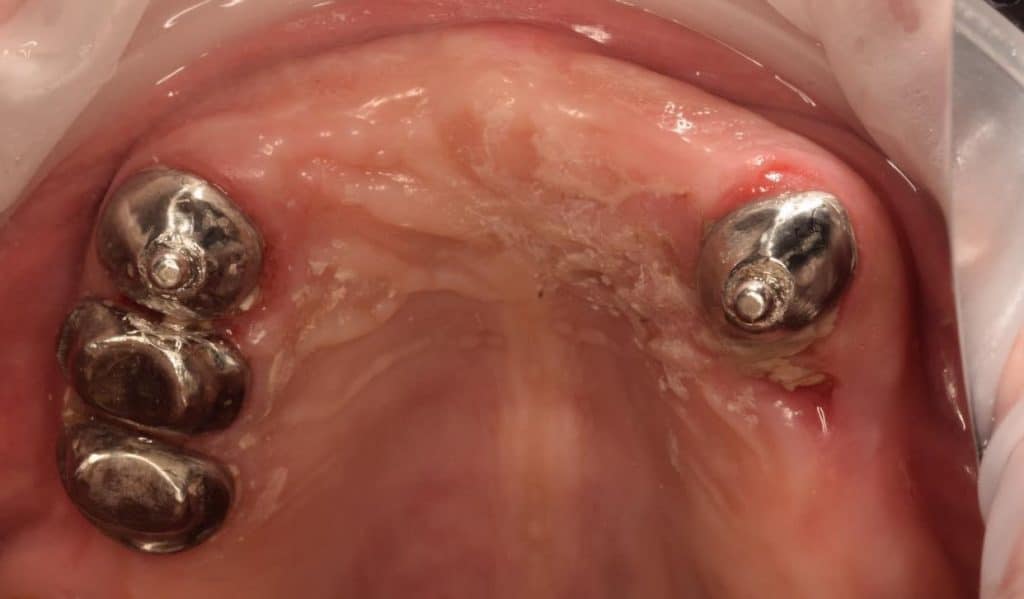

4th clinical visit:

Primary copings ( inner telescopic crown ) and male part ( ball ) were seated intraorally to check for their margin and fitting. Primary copings and male part were cemented in patient’s mouth with RMGI luting cement (self cured , riva , Australia)